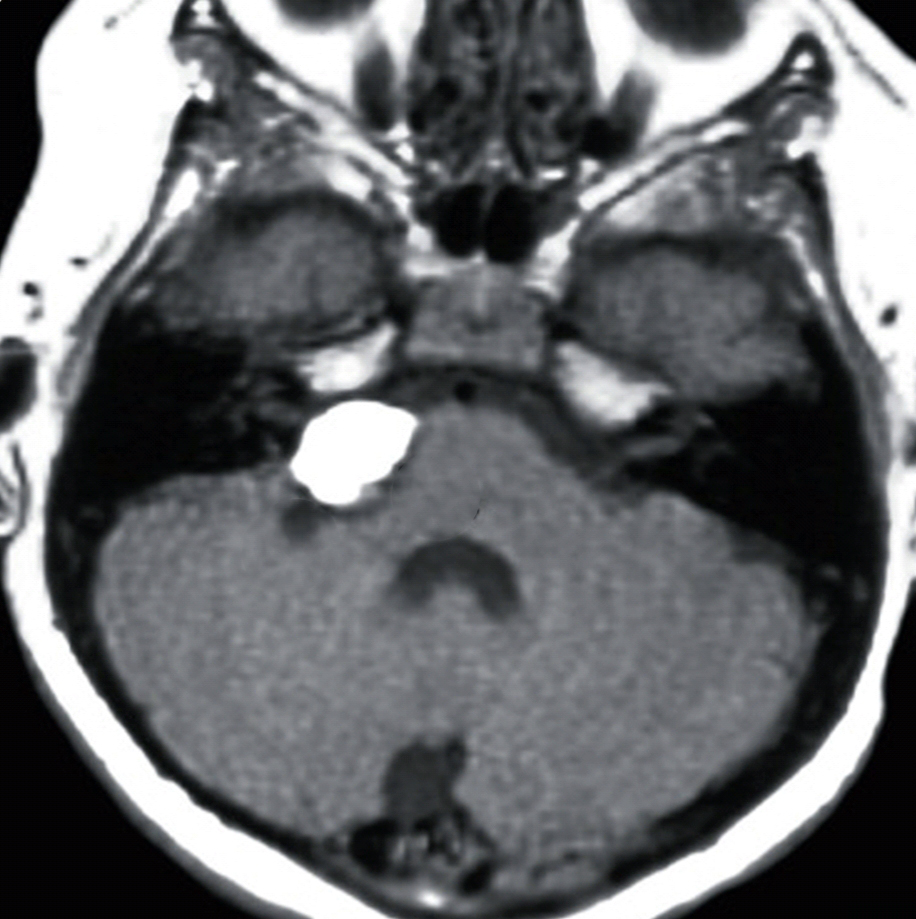

From www.radiomind.org

Intracranial lipoma Velum Interpositum Lipoma small pericallosal lesion around the inferior aspect of the splenium centered on the cavum velum interpositum with lateral. the velum interpositum is a small membrane containing a potential space just above and anterior to the pineal gland which can become. the lipomas that did not demonstrate csas at 1.5 t were all less than 1 em in. Velum Interpositum Lipoma.

Intracranial lipoma Velum Interpositum Lipoma the velum interpositum (vi) is a membrane resulting from the superposition of two. small pericallosal lesion around the inferior aspect of the splenium centered on the cavum velum interpositum with lateral. intracranial lipomas are rare congenital malformations which are present in choroid plexus or subarachnoid. the velum interpositum is a triangular space between the two layers. Velum Interpositum Lipoma.